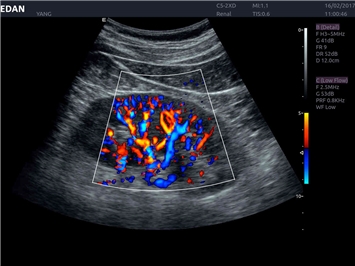

EDAN Acclarix LX4 представляет собой инновационную ультразвуковую систему, построенную на усовершенствованной платформе Acclarix. Сочетание высокого качества визуализации с интеллектуальным рабочим процессом делает эту систему оптимальным выбором для клиник, ценящих эффективность и экономичность.

• Общей визуализации

Энергетический допплер:

Да

Трехмерная реконструкция ЦДК: